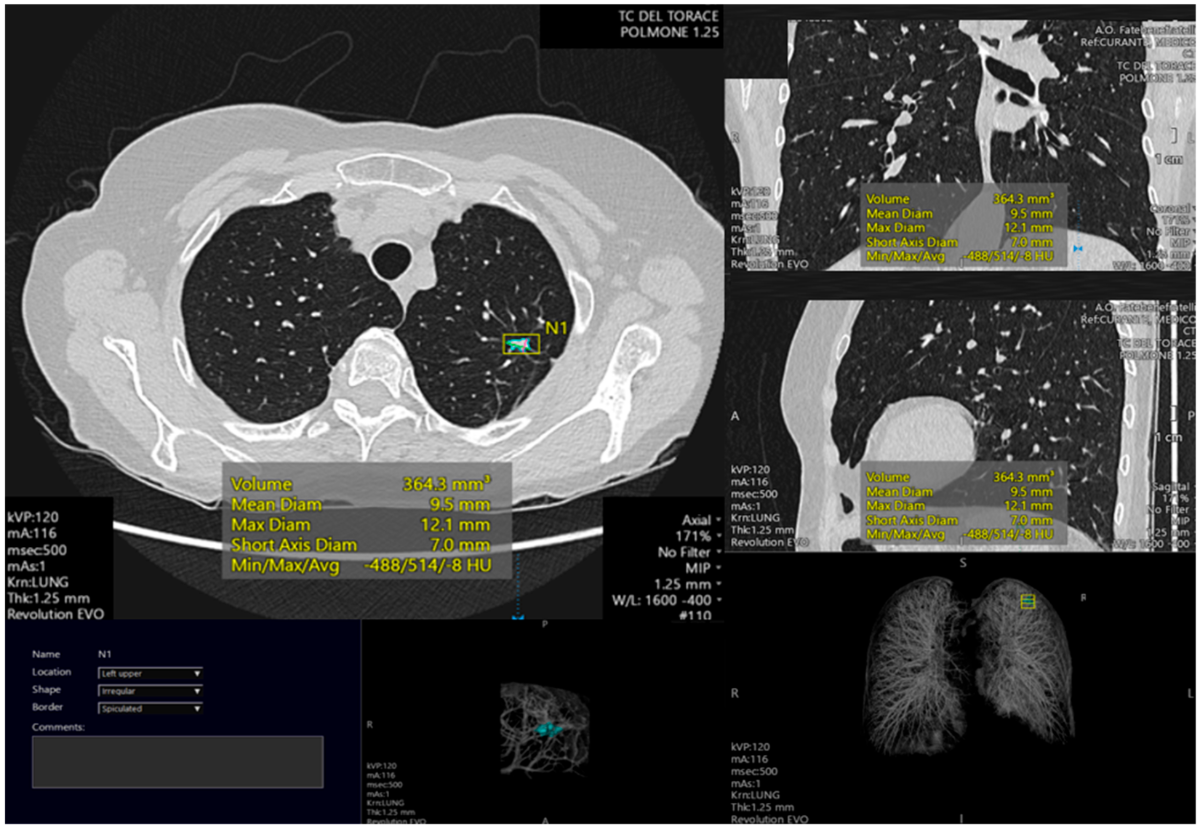

Song song, trí tuệ nhân tạo (AI) đang được đưa vào ứng dụng trong chẩn đoán ung thư. Như Bệnh viện Bạch Mai đang triển khai đề tài cấp Nhà nước sử dụng AI trong phân tích hình ảnh CT, nội soi phế quản và mô bệnh học để tầm soát, phát hiện sớm ung thư.

Kết quả bước đầu cho thấy AI có khả năng đánh giá nguy cơ mắc ung thư với độ chính xác cao. Công nghệ này cũng đang được thử nghiệm trong siêu âm tuyến giáp, siêu âm và chụp X-quang vú, hỗ trợ bác sĩ trong việc phát hiện sớm bệnh lý ác tính.